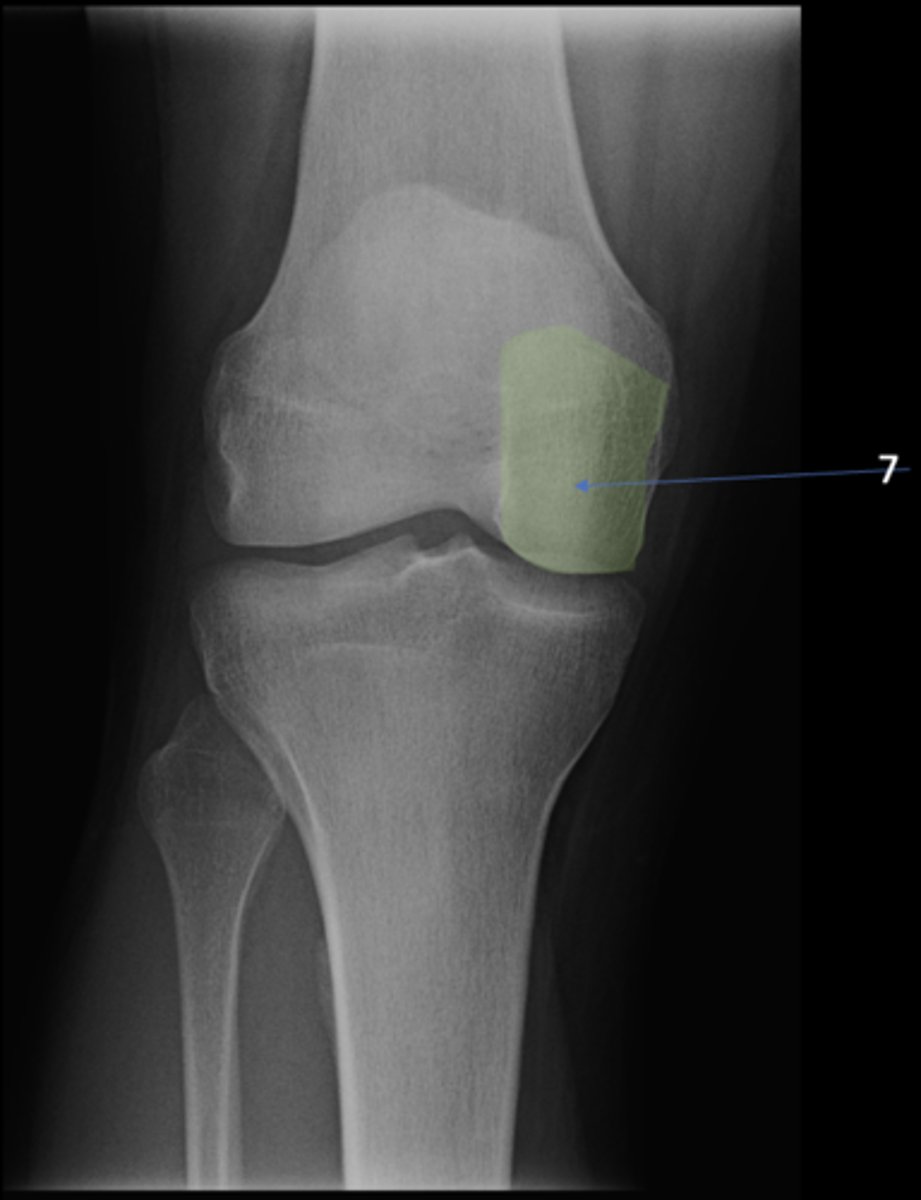

7

New cards

Right ischium

ID 7

<p>ID 7</p>